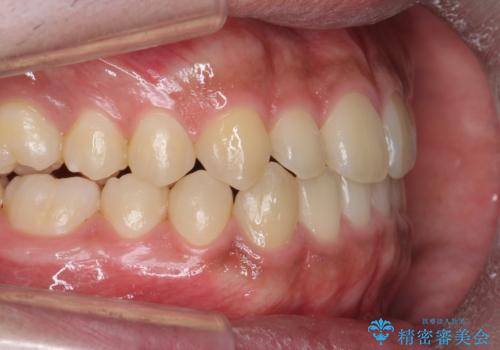

骨格性の受け口 非抜歯で下の歯を後ろに下げる インビザラインで インプラント矯正

- 受け口を主訴に来院。

治療により受け口が改善し、下あごの輪郭も若干後ろに下がった印象になりました。

某格安マウスピース病院での担当医の説明に不信感を持ったとのことでした。話を聞く限りですが、治療のゴールは患者様が決めると説明をしたなど、治療計画も骨格的に受け口の方に対するアプローチとしてはずさんな印象を受けました。

一見簡単そうにみえて、前歯の反対咬合を入れ替える際は一時的に奥歯もかみ合わない状態になります。

顎のずれが大きい場合はそれだけでは治療できないことが多いです。

当院では下の歯を後ろに下げるため矯正用ミニスクリューを用いてしっかり移動を行う等ご説明をし、治療開始しました。